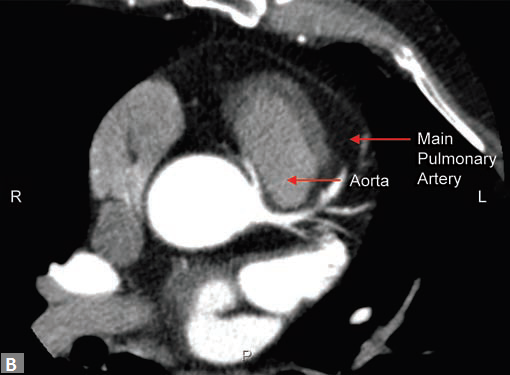

Filling defects (Figs 16A and B) may be seen in main

pulmonary artery (MPA), left pulmonary artery (LPA) and

right pulmonary artery (RPA), interlobar artery, segmental

divisions (Figs 17A and B). On occasions, detection in distal

parts of segmental divisions is difficult. This can be further

confounded by motion artifacts, non- or minimally opacified

accompanying pulmonary veins.

Mural calcification suggests chronicity of thromboembolism.

Bronchial and other systemic collaterals,

dilated MPA (> 28.5 mm) are also indicators of chronicity.